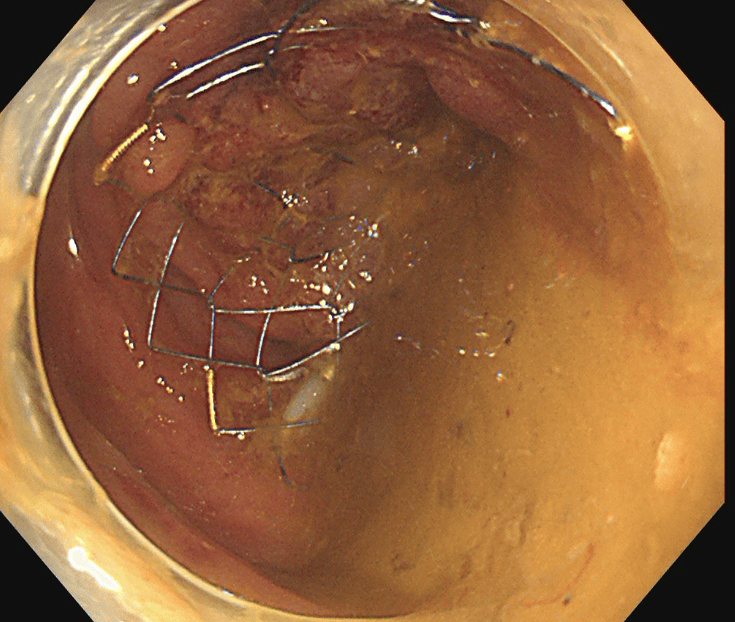

閉塞性大腸がんに対する大腸ステント治療

大腸がんが進行し腸が詰まってしまう閉塞性大腸がん(大腸がん腸閉塞)に対する治療です。従来は人工肛門を造設して対処していましたが、人工肛門はケアの負担やにおいに対する不安などからQOL(生活の質)低下が避けられません。そのため当院ではステントと言われるメッシュ構造の金属製の網を用いて詰まりを解消し、人工肛門を回避する治療を行っています。大腸ステント治療は緩和治療を目的に行う場合と根治手術前に全身状態の回復を目的として行う場合があります。

治療前

ステント留置後(内視鏡画像)

ステント留置後(レントゲン画像)